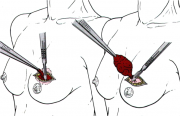

| 15:48, 8 בספטמבר 2012 | שיטותפולשניות1.jpg (קובץ) |  |

9 קילו־בייטים | Nachi | 1 | |

| 15:49, 8 בספטמבר 2012 | שיטותפולשניות2.jpg (קובץ) |  |

15 קילו־בייטים | Nachi | 1 | |

| 15:49, 8 בספטמבר 2012 | שיטותפולשניות3.jpg (קובץ) |  |

10 קילו־בייטים | Nachi | 1 | |

| 15:50, 8 בספטמבר 2012 | שיטותפולשניות4.jpg (קובץ) |  |

5 קילו־בייטים | Nachi | 1 | |

| 15:50, 8 בספטמבר 2012 | שיטותפולשניות5.jpg (קובץ) |  |

7 קילו־בייטים | Nachi | 1 | |

| 15:50, 8 בספטמבר 2012 | שיטותפולשניות6.jpg (קובץ) |  |

7 קילו־בייטים | Nachi | 1 | |